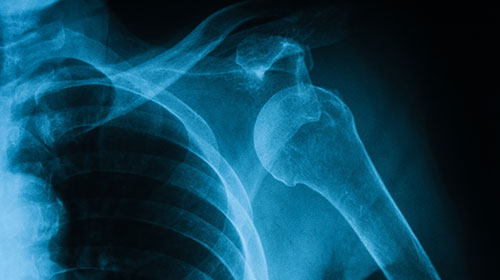

Imaging

Imaging Services at all Northside Hospital Orthopedics - Sports Medicine Specialists

Expert imaging services are available on-site at all Northside Hospital Orthopedics - Sports Medicine Specialists locations. With state-of-the-art equipment and convenient diagnostic testing services, our team offers imaging services for prompt and accurate diagnosis and treatment planning.